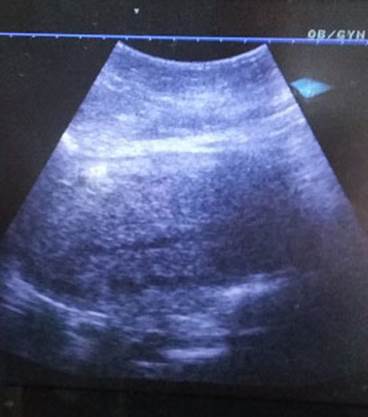

Se retiró balón endouterino 24h posterior al parto y la evolución clínica de la puérpera fue satisfactoria, logrando contracción uterina y comprobación ecográfica de la línea endometrial. (Figura 3). Se indicó profilaxis antimicrobiana de amplio espectro y de la enfermedad trombo embólica. La paciente fue egresada siete días después del parto, con una involución puerperal adecuada y sin otras complicaciones.